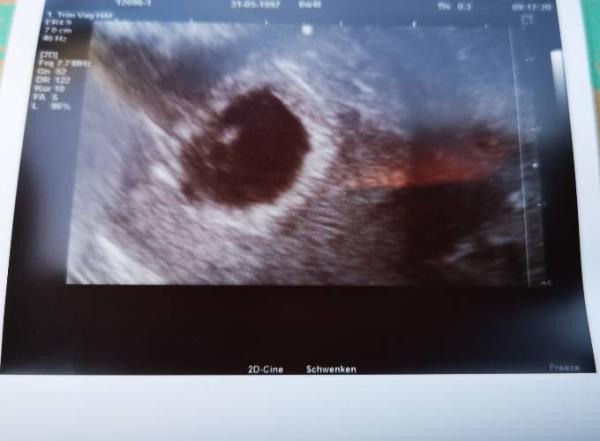

... Und ich bin überglücklich, endlich habe ich es schwarz auf weiß gesehen das da ein kleines Leben in mir heranwächst Ich konnte im Ultraschall auch schon das Herzchen schlagen sehen... Meine Frauenärztin meinte das alles gut ist, laut Rechnung müsste ich heute 6+4 sein aber auf dem Ultraschallgerät stand nach der Messung 5+5,krümel ist 3 mm groß, das ist das einzige was mich ganz leicht verunsichert, aber ich habe in 2 Wochen wieder einen Termin

Bild zu 1. FA Termin... - Forum für Januar - Mamis